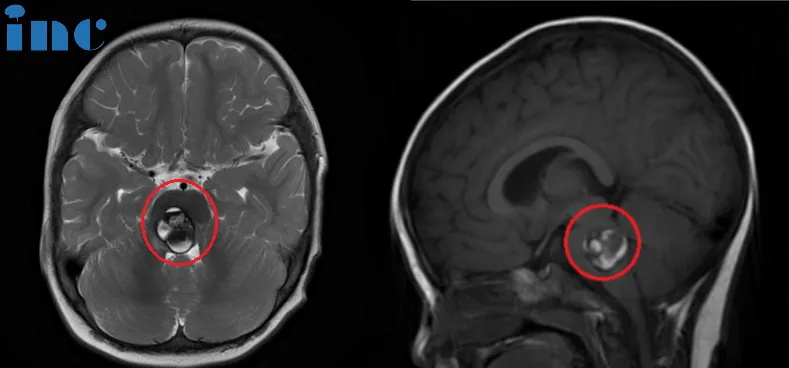

术前:脑桥占位。双眼斜视、畏光,面瘫,频发不自主扭头动作,走路稍有不稳。头颅MR(红色区域)显示:脑桥血肿,可见16 x 22 x 21mm肿块,四脑室受压变窄。

术后:头颅MR(蓝色区域)显示小脑半球及脑干形态正常,中线结构居中,原脑桥内团块状信号消失。